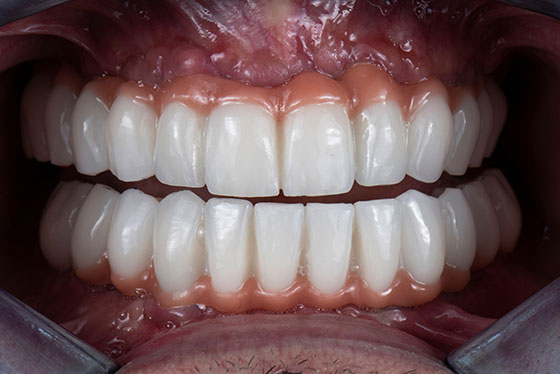

All-on-4では、インプラントで固定された土台の上に歯を装着するため、入れ歯のように外れてしまう心配が少なく、おしゃべりやお食事も、より自然に楽しめます。

All-on-4では、上下それぞれの顎に12本の歯が入ります。上下ともに治療を行う場合、症例によっては、手術当日からすべての歯が入り、噛める状態を目指すことも可能です。

長い間、噛めない状態や見た目に悩まれてきた方にとって、「その日から噛める」というのは、とても大きな安心感につながります。